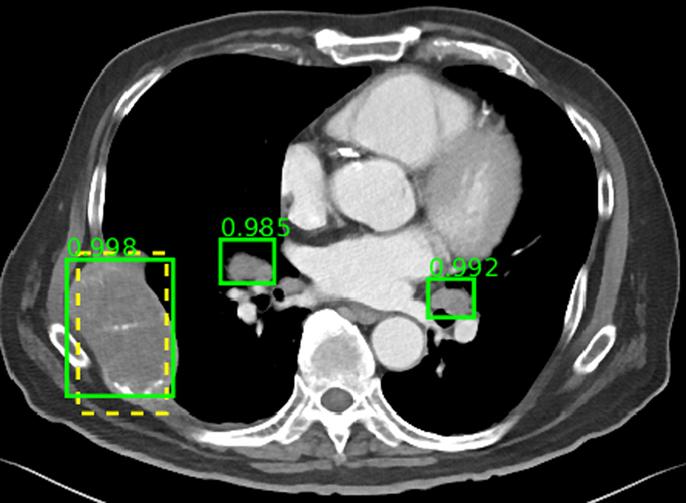

image: The ground-truth and two enlarged lymph nodes are correctly detected, even though the lymph nodes are not annotated in the dataset. view more

The database includes multiple lesion types, including kidney lesions, bone lesions, lung nodules, and enlarged lymph nodes. The lack of a multi-category lesion dataset to date has been a major roadblock to development of more universal CADe frameworks capable of detecting multiple lesion types. A multi-category lesion dataset could even enable development of CADx systems that automate radiological diagnosis.

In addition to building the database, the team also developed a universal lesion detector based on the database. The researchers note that lesion detection is a time-consuming task for radiologists, but a key part of diagnosis. This detector may be able to serve as an initial screening tool for radiologists or other specialist CADe systems in the future.